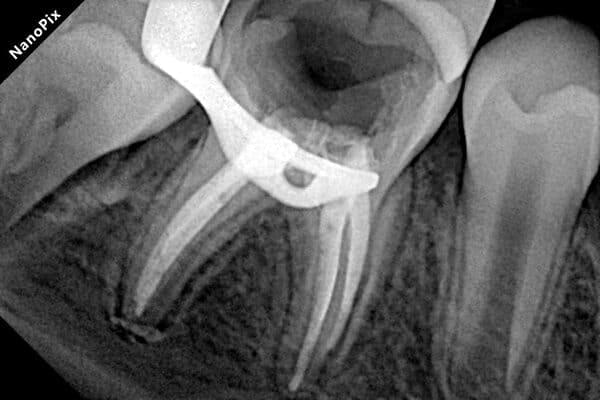

Робота з несформованими постійними зубами — найскладніша маніпуляція в дитячій стоматології. Ці зуби мають особливу будову, що ускладнює їх очищення та пломбування. У нашому Центрі Дитячої Стоматології в Києві ми володіємо передовими методиками, які дозволяють врятувати навіть найскладніші зуби.

Пульпа (нерв) постійного зуба має величезний потенціал до відновлення. Якщо це можливо, ми зберігаємо її, адже саме вона відповідає за ріст і повноцінне формування кореня. Зуб зі сформованим коренем значно міцніший і витриваліший.

Якщо ж пульпа не підлягає збереженню, ми використовуємо спеціалізовані методики та матеріали, які дозволяють закрити верхівки кореня перед пломбуванням. Це забезпечує надійний результат і запобігає ускладненням.